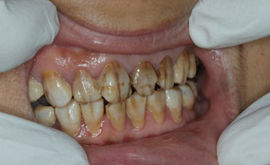

1、氟斑牙的特点。是在同一时期萌出的釉质上有白垩色到褐色的斑块,严重者还并发有釉质的实质缺损。临床上常按其轻、中、重度而分为白垩型(轻度)、变色型(中度)和缺损型(重度)三种类型:

中度氟斑牙——牙面出现黄色、黄褐或棕褐色;

重度氟斑牙——除上述改变以外,牙面还出现浅窝或坑凹状缺损,或因磨损使牙失去正常外形。

中富口腔医师介绍,严重的氟斑牙不仅有严重的着色,而且还会出现缺损,因而这样的情况,普通的牙齿美白是达不到理想的效果的,只能通过瓷贴面的方式才能够实现色泽与形态的双向改变。